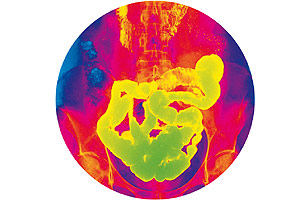

Sistema digestivo: el sistema que te alimenta

Si tuvieras que imaginarte lo que sucede en tu organismo cada vez que comes, tendrías que pensar en una enorme tormenta en el mar. El mar y la lluvia serían el jugo gástrico y los ácidos participantes en la degradación de los alimentos. La comida representaría una embarcación en medio de agitados movimientos hacia uno y otro lado de tu estómago.